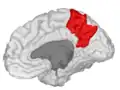

| Precuneus | |

![]() Medial surface of left cerebral hemisphere. (Precuneus visible at top left.) (Anterior to the right.) | |

Precuneus of left cerebral hemisphere (shown in red).

Medial surface of left cerebral hemisphere. (Precuneus visible at top left.)

Medial surface of left cerebral hemisphere. (Precuneus colored in red.)